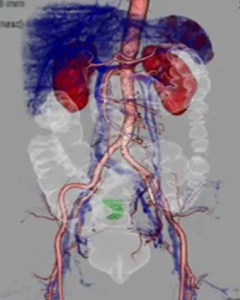

検出器の多列化により短時間に広範囲の撮影が可能となりました。また1度の撮影で様々な断面画像を得られます。得られた画像をワークステーションで解析することで3D画像を作成できます。

造影剤を使用することで病変や血管を詳細に描出できるため病変部の血管走行を把握することができます。血管走行の3Dは手術プランに役立てられます。- 腰部血管3D

- 頭部動静脈3D